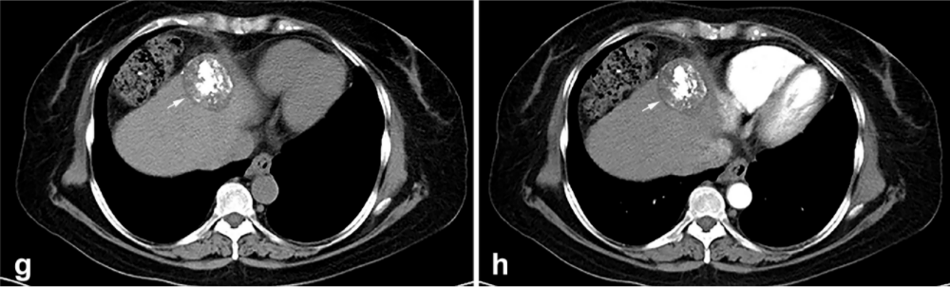

背景:由于一些原因,位于膈肌附近的肿瘤的热消融在技术上具有挑战性。首先,术中计算机扫描和超声检查无法清晰显示射频消融/微波消融切缘。第二,消融过程中不利的针分布和过热可能导致肝包膜破裂,并对膈、肺和心脏造成严重损伤。第三,即使使用人工腹水,仍有9~22%的患者因肝周粘连或肿瘤位置靠近肝表面而导致膈肌热损伤。冷冻消融可能是毗邻膈肌的HCC的一种有前途的治疗方法,因为在消融过程中使用CT和US可以很好地显示肿瘤边缘。尽管一些研究评估了在高危区域使用冷冻消融治疗HCC,但很少有研究针对膈肌临近区域。